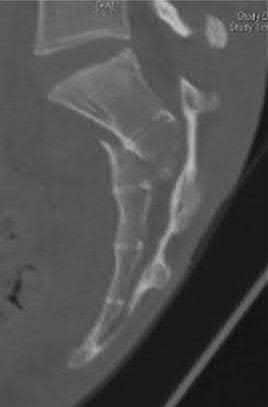

Question 9:

A 24-year-old professional football player sustains a high-energy axial load injury to a plantarflexed foot. Radiographs demonstrate widening of the midfoot spaces. The critical interosseous Lisfranc ligament connects which of the following two osseous structures?

Correct Answer: Medial cuneiform to the base of the second metatarsal

Explanation:

The Lisfranc ligament is a strong interosseous ligament critical for the stability of the tarsometatarsal joint complex. It originates from the lateral aspect of the medial cuneiform and inserts onto the medial aspect of the base of the second metatarsal. There is no direct ligamentous connection between the bases of the first and second metatarsals, making the Lisfranc ligament the primary restraint to lateral displacement of the lesser metatarsals.